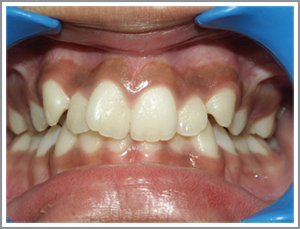

Case 4

Before

After

XYZ a 14 year old girl presented with the mild protrusion of her front teeth and mild irregularity. (Angles class I mildbimaxillaryproclination and mild crowding)

Problem list : Teeth had a poor appearance due to irregularity.Lips looking too protrusive when they were closed.

Treatment plan : extraction case – case was treated with the extraction of four first premolars. The front teeth (incisors and canines) were then taken back and aligned the patient had a pleasing appearance and her lips were less protrusive.

Treatment time : 20 months